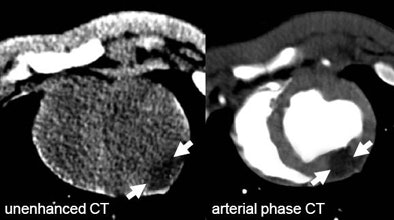

| The arrows on unenhanced CT show a hypodense area corresponding to edema as it can be seen on T2-weighetd MRI. The arrows on late-phase CT and MR correspond to infarction. The area of edema is larger than the area of infarction as expected based on previous MRI studies for the imaging of myocardial edema. All images courtesy of Dr. Andreas Mahnken. |

According to the results, mean MI sizes on unenhanced, arterial, and late-phase DSCT were 27.2 ± 8.5%, 20.1 ± 6.9%, and 23.1 ± 8.2%, respectively. The corresponding values on T2-weighted and delayed enhanced CMR were 28.5 ± 7.8% and 22.2 ± 7.7%. Size of MI on TTC staining was 22.6 ± 7.8%.

The best agreement was found in the comparison between late-phase CT (pc = 0.9356) and delayed enhanced CMR (pc = 0.9248) with TTC staining. The group also found substantial agreement between unenhanced DSCT and the T2-weighted CMR images (pc = 0.8629).

Unenhanced DSCT offered the lowest percent signal difference (46.0 ± 18.3) and the lowest contrast-to-noise ratio (4.7 ± 2.0) between infarcted and healthy myocardium, they reported.

The study shows that "unenhanced DSCT provides different information about acute ischemic injury when compared with arterial and late-phase CT," Mahnken et al wrote. "Simple theoretical consideration led to the hypothesis that hypodense areas within the [left ventricular (LV)] myocardium correspond to edema, because increased tissue water content should result in a decrease of the CT values when compared with healthy myocardium."